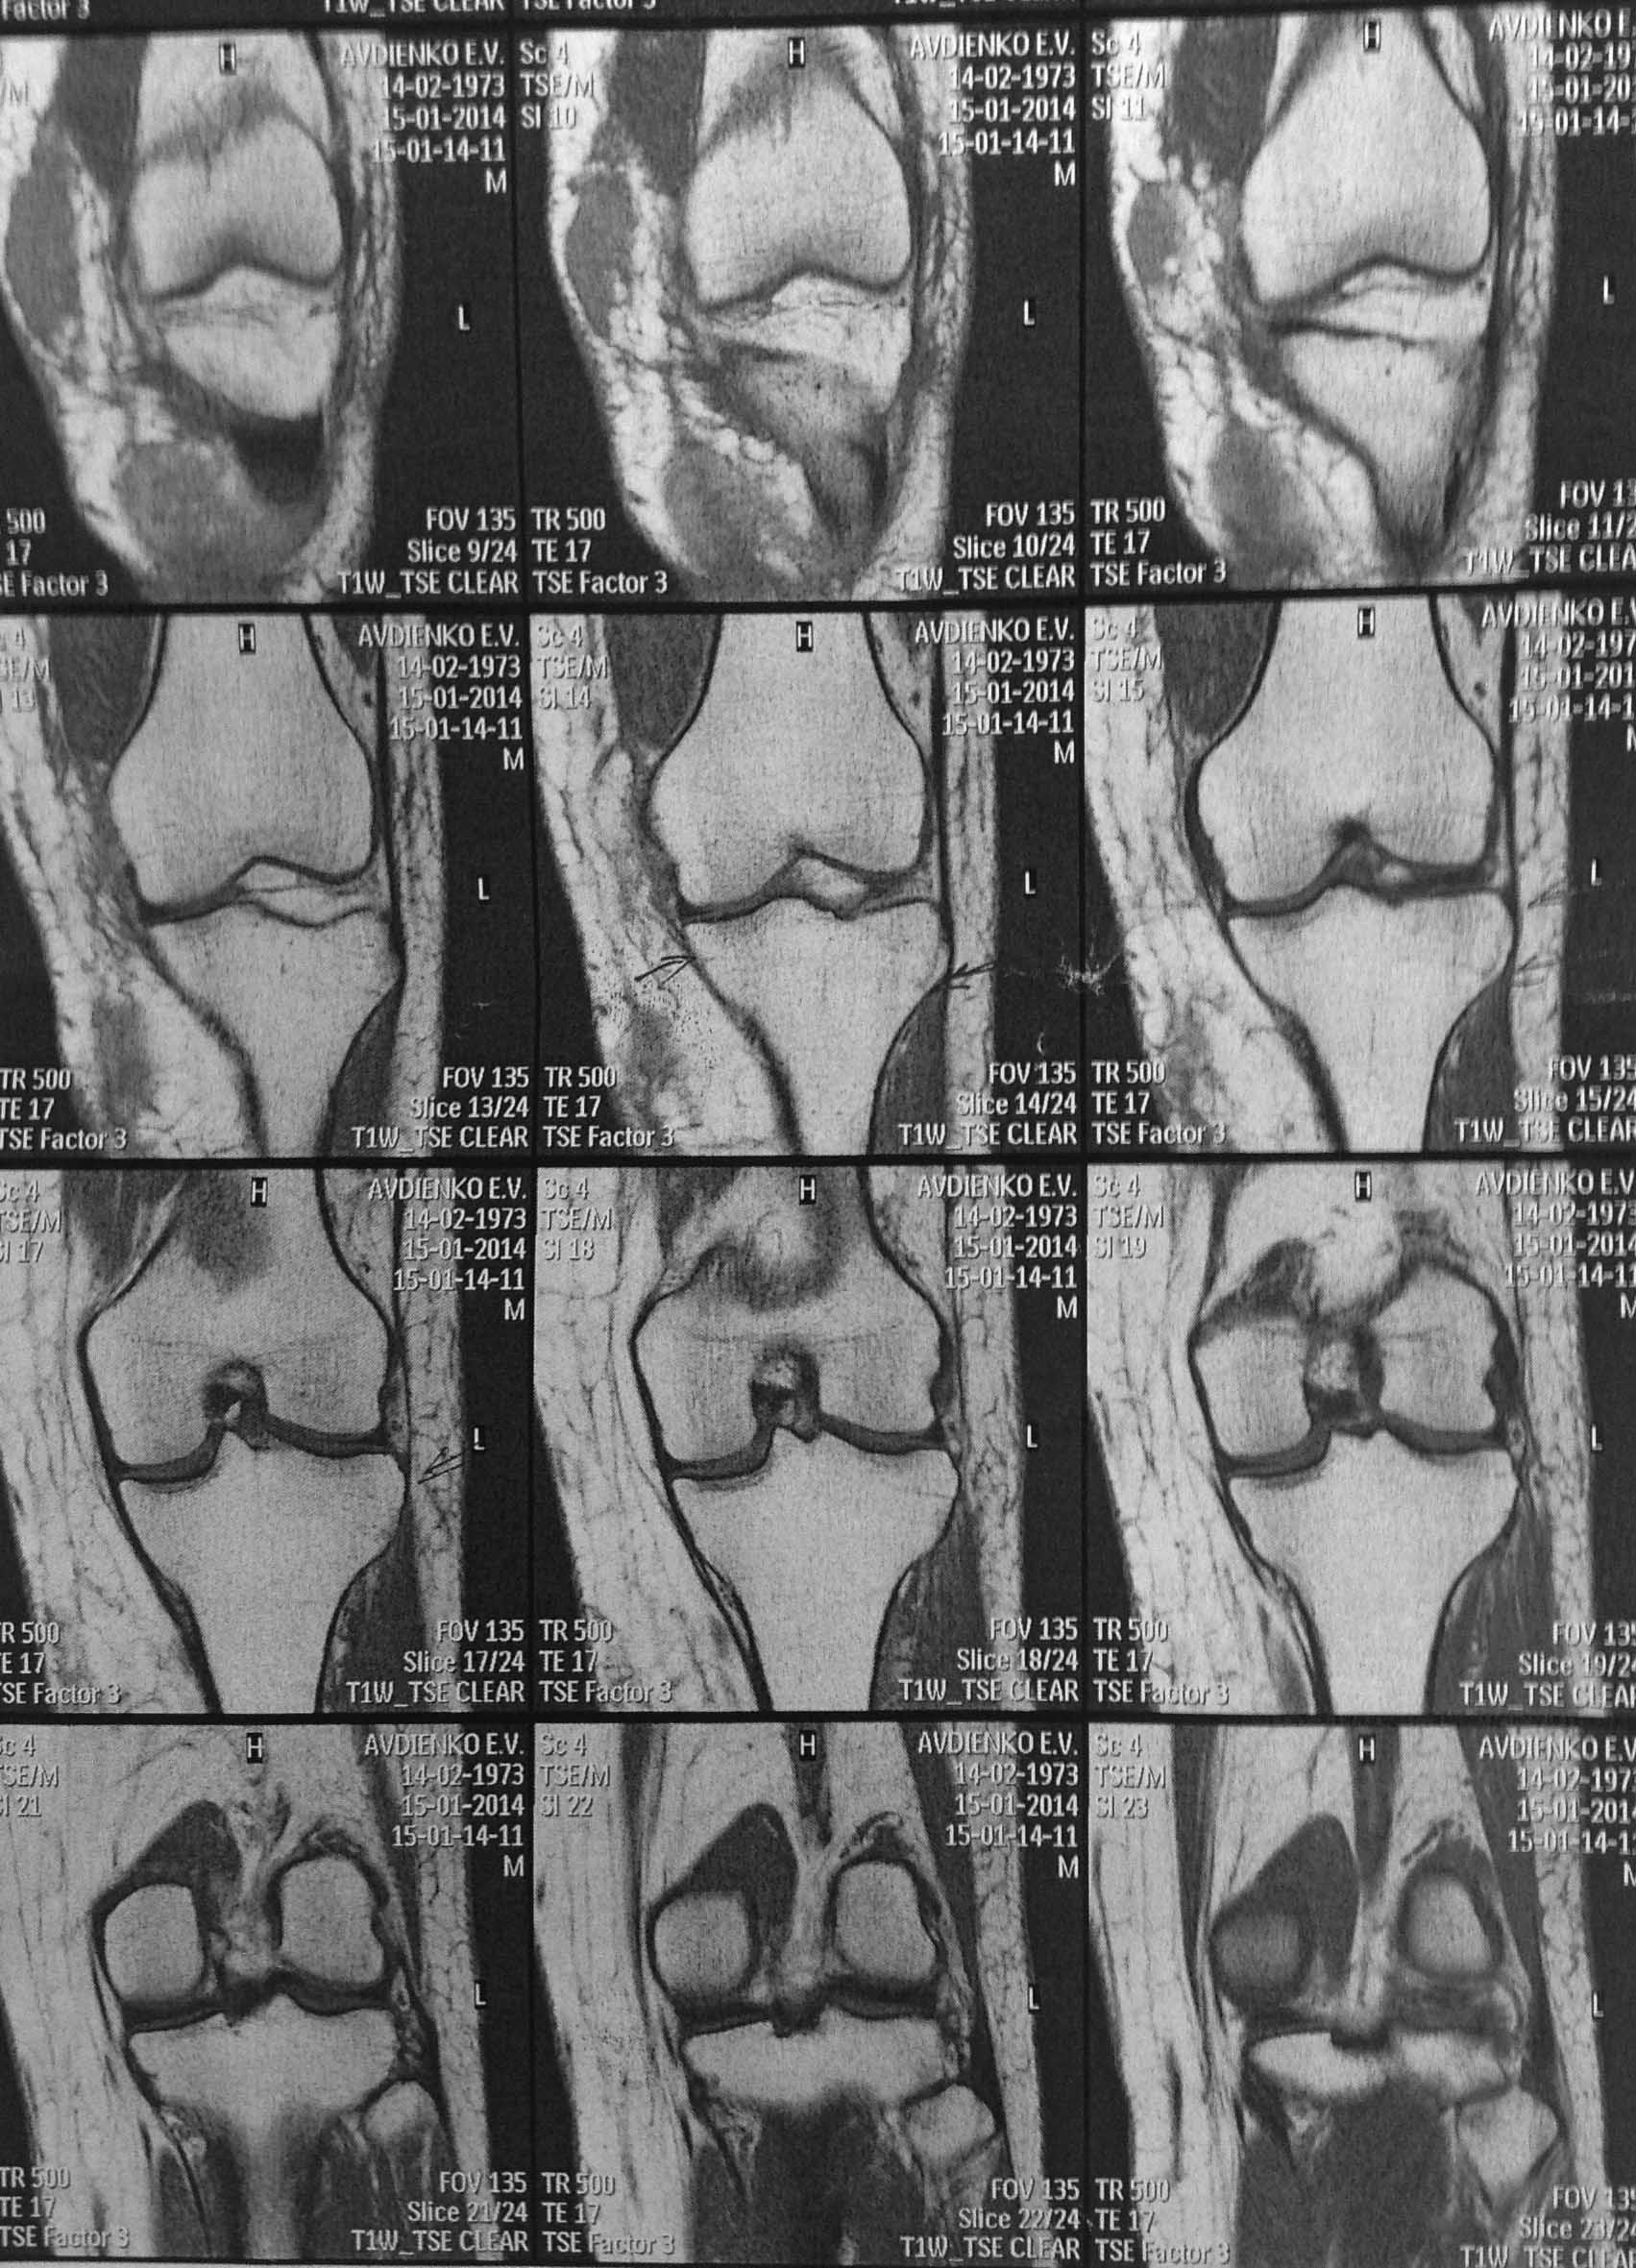

Уважаемые коллеги? Понимаю несуразность поста, но все же. Пациентка Ж 40 лет, травма ДТП 29.12.13, по месту получения травмы вскрыта межмышечная гематома, иммобилизация тутором.

Объективо- движения в коленном суставе 0/0/0, связочный аппарат стабилен. НО САМОЕ консультация профессора ( дама не из простой семьи) - и вердикт - оскольчатый внутри суставной перелом наружного мыщелка большеберцовой кости и лечение- 3 месяца постоянный тутор. Меня чуть на ноль не умножали, что я пропустил перелом в таком важном месте. Коллеги!!!!!! А был ли мальчик, вглядитесь пожалуйста и вынести решение!!!!!!!

Можно заподозрить минимальную импрессию наружного мыщелка, но и то только когда начинаешь вглядываться...скорее всего спор может разрешить только артроскопия коленного сустава.

я тоже перелома не вижу, ровно как и других серьезных повреждений

То, что указано стрелками, называется в рентгенологии "посттравматический отек костного мозга"

Отек костного мозга был бы лучше виден в Т2-режиме, а там вообще ничего нет / или тех срезов где что-то есть не представлено.

Кроме того, стрелочки на кортикал направлены, а не в костный мозг:)

ТО, что помечено стрелочками - это вообще ничто, таких стрелочек можно на любом скане с десяток нарисовать и щеки раздувать.

1. Перелома не видно

2. Если продолжать спорить, то нужно РКТ а не МРТ, и, согласен, лучше артроскопия.

Представьте пожалуйста фронтальные сканы в Т2 режиме, а то сравниваем Т1-фронтальный с Т2-сагиттальным.

По Т1 никаких нарушений анатомии нет. Если на Т2 будет белое "пятно" - тот самый "ушиб костного мозга", то рентгенолог сможет написать про перелом. Причем следы этого ушиба могут сохраняться на МРТ до нескольких недель. Но на тактику лечения это никак не повлияет - никакой "нестабильности костных фрагментов" тут и в помине не будет - посему ранние движения, а нагрузка по мере исчезновения болезненности (фразы общие, но вопрос об этом и не стоит?).

Импрессионного,тем более оскольчатого, перелома наружного мыщелка нет.